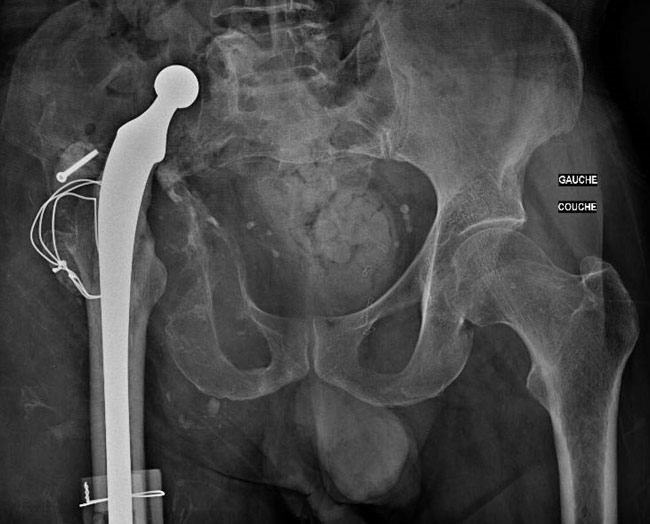

Pre-op x-ray